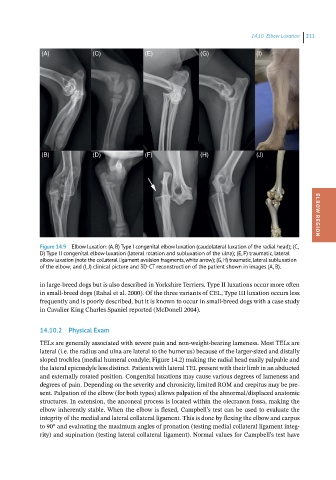

Figure 14.9 Elbow luxation: (A, B) Type I congenital elbow luxation (caudolateral luxation of the radial head); (C, ELBOW REGION

D) Type II congenital elbow luxation (lateral rotation and subluxation of the ulna); (E, F) traumatic, lateral

elbow luxation (note the collateral ligament avulsion fragments, white arrow); (G, H) traumatic, lateral subluxation

of the elbow; and (I, J) clinical picture and 3D-CT reconstruction of the patient shown in images (A, B).